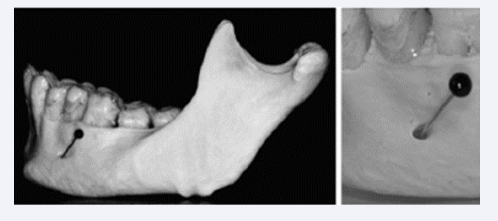

The mandibular canal was first observed on anthropological material after 20 weeks of age. The nerve fibers in the mandibular inferior nerve were gradually encircled by bone tissue, resulting in formation of the mandibular canal [15-18]. The first peripheral nerves which was encircled was the nerves to the incisors located in the lower aspect of the canal and these were followed by the nerves to the canines and molars located in the upper aspects of the canal [Figure 10].

Figure 10 Two human anthropological mandibles from about 30 weeks of Gestation illustrate the initial formation of the alveolar inferior nerve  and the mandibular canal. Left mandible is observed from the lingual side with gutta-percha points ( root filling sticks) resembling peripheral  nerves inserted in different holes. Right mandible observed from above. In this figure the gutta-percha points indicate that the peripheral nerves  have different directions and are located in different levels.

Figure 10: Two human anthropological mandibles from about 30 weeks of Gestation illustrate the initial formation of the alveolar inferior nerve and the mandibular canal. Left mandible is observed from the lingual side with gutta-percha points ( root filling sticks) resembling peripheral nerves inserted in different holes. Right mandible observed from above. In this figure the gutta-percha points indicate that the peripheral nerves have different directions and are located in different levels.